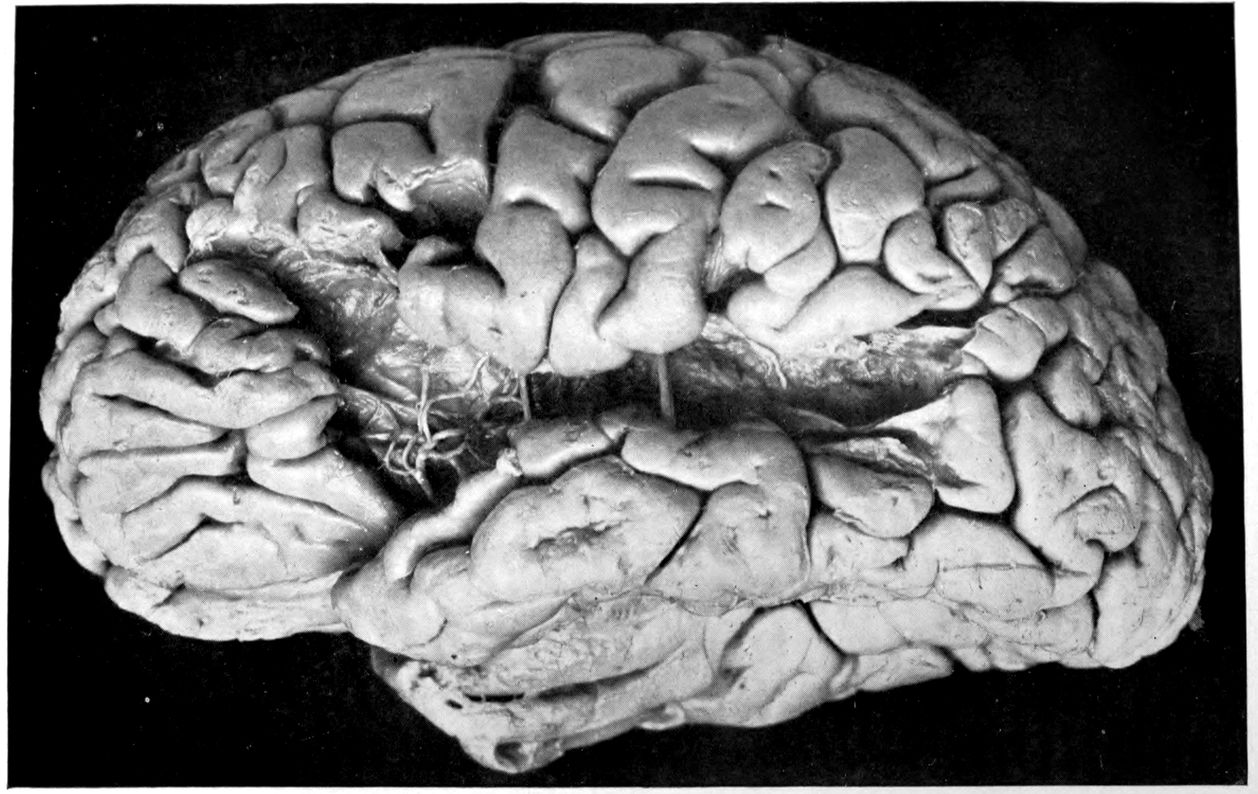

VASCULAR NEUROSYPHILIS (“syphilitic cerebral thrombosis”). Autopsy.

Case 4. James Pierce was an almshouse transfer to the Danvers Hospital in his fiftieth year. He died three years later. The accompanying brain pictures demonstrate so extensive a lesion of the left hemisphere that it is of great interest to determine if possible the genesis and course of his disease. It appears that syphilis had been acquired somewhere about the age of 38 or 40, so that the total duration of the process was between 13 and 15 years. In Pierce’s forty-third or forty-fourth year, he had a shock while walking in the streets of his native city, whereupon he was subsequently transferred to the Danvers Hospital, whose data have been summed up as follows (we are obliged to Dr. Charles T. Ryder for these data):

The autopsy findings were as follows:

Head: Calvarium of moderate thickness; diploë present; dura slightly adherent over bregmatic region. Longitudinal sinus contains cruor clot. Dura is somewhat thickened and slightly more opaque than normal. Pacchionian granulations, small but fairly numerous. Pia contains throughout a considerable excess of clear 44serous fluid. The convolutions in general are of good breadth and proportion. There is an atrophic area roughly circular in outline and about 2 cm. in diameter in the posterior part of the right third frontal convolution corresponding to Broca’s area on the opposite hemisphere. The space thus formed is filled with edema held by the pia. On the left side is a similar subpial collection which covers the site of the posterior portions of all of the third frontal convolutions, parts of the lower end of the precentral convolution, and the whole of the first temporal convolution, which have disappeared entirely. The basal vessels show slight changes.

Cerebellum and basal ganglia are grossly normal.

The spinal membranes are negative. The regions of the pyramidal tracts in the cord are firm, project slightly from surface of section, and are china white.

Summary: Here is a picture made up almost purely of Vascular Neurosyphilis, with Secondary Spinal (Pyramidal Tract) Changes. Doubtless the genesis of this picture is allied to that of Case 1 (Alice Morton) and to that of the terminal vascular complications in a tabetic, Case 2 (Francis Garfield).

The absence of meningeal and parenchymatous (i.e., outside the region of necrosis produced by the vascular disease) lesions is characteristic of an important group of neurosyphilitic diseases. It is clear that the case, although one of extensive lesions, is not one of diffuse lesions in the sense of Case 1 (Alice Morton).

Vascular neurosyphilis—effects of syphilitic thrombosis of Sylvian artery 10 years before death. (Case 4.)